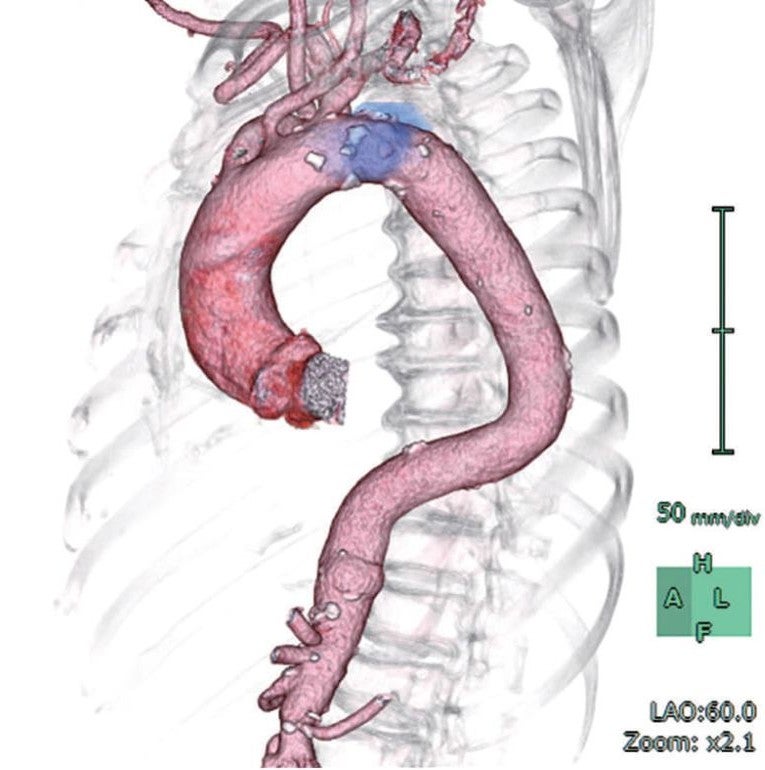

− 遠位弓部大動脈瘤(囊状瘤:最大径56 mm 拡張部23 mm)

- 本症例は、中枢ランディング長:20 mmの遠位弓部大動脈瘤(囊状瘤)で、Zone 2ランディング+左鎖骨下動脈単純閉鎖の方針とした 。中枢ネック径:33 mm、末梢ネック径:30 mmと計測値 であったが、通常弓部大動脈領域ではコアキシャルに留置されないことから、斜めに計測しデバイスサイズを決定する。その場合中枢ネック径は34.5 mmとなり、推奨デバイス径は40 mm デバイスとなり、末梢ネック径:30 mmにおいては33% オーバーサイズとなる 。しかしながら、アンギュレーションコントロールにてコアキシャルに留置できれば、37 mmデバイス1本で推奨サイズ径となる。右上腕動脈よりピッグテールカテーテルを留置した。

- デバイス留置後、左鎖骨下動脈根部で造影し、コイル塞栓施行の判断をする方針とした 。 ガイドワイヤーに関しては、上行大動脈径を測定し、35 mm径であることからEgoist® EGU35-AC300Q (Arch Curve)* を選択し、50 mmシリンジを用いて先端部分をmanipulateした。(図1、2)